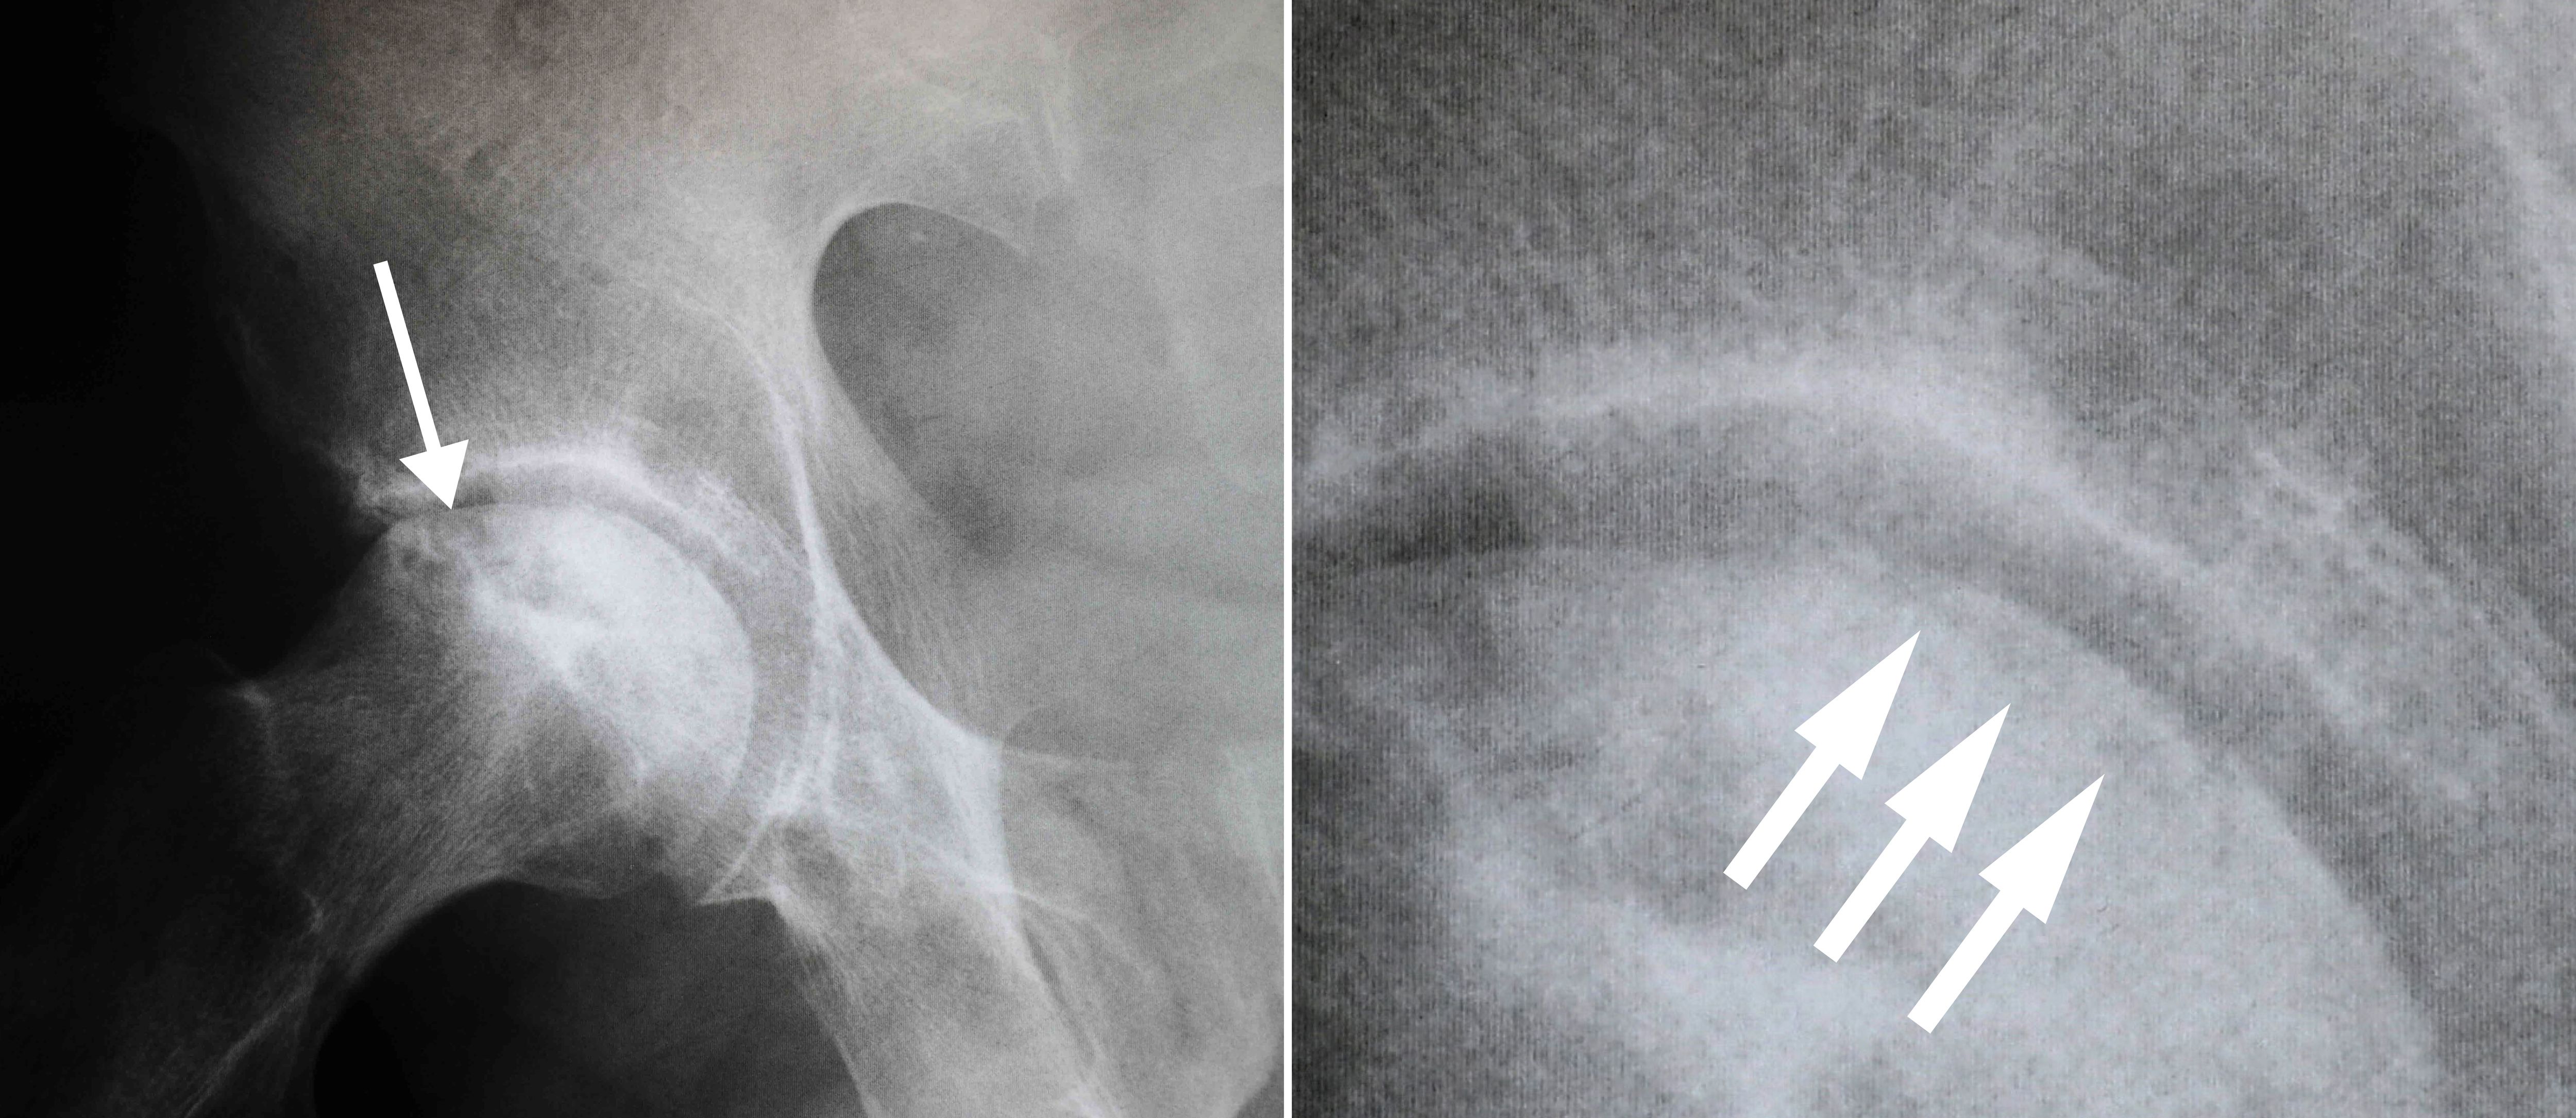

Osteonecrosis is typically seen as a wedge-shaped area with a dense whitish sclerotic (hardened) border in the superior lateral portion of the femoral head. On the lateral view, a line called a “crescent sign” can often be seen just below the surface of the femoral head.

Osteonecrosis of the hip

(Left) This X-ray shows osteonecrosis of the hip. (Right) When viewed close up, the X-ray reveals the “crescent sign” that is typically seen before collapse of the femoral head.

Images courtesy of Stuart J. Fischer, MD, FAAOS